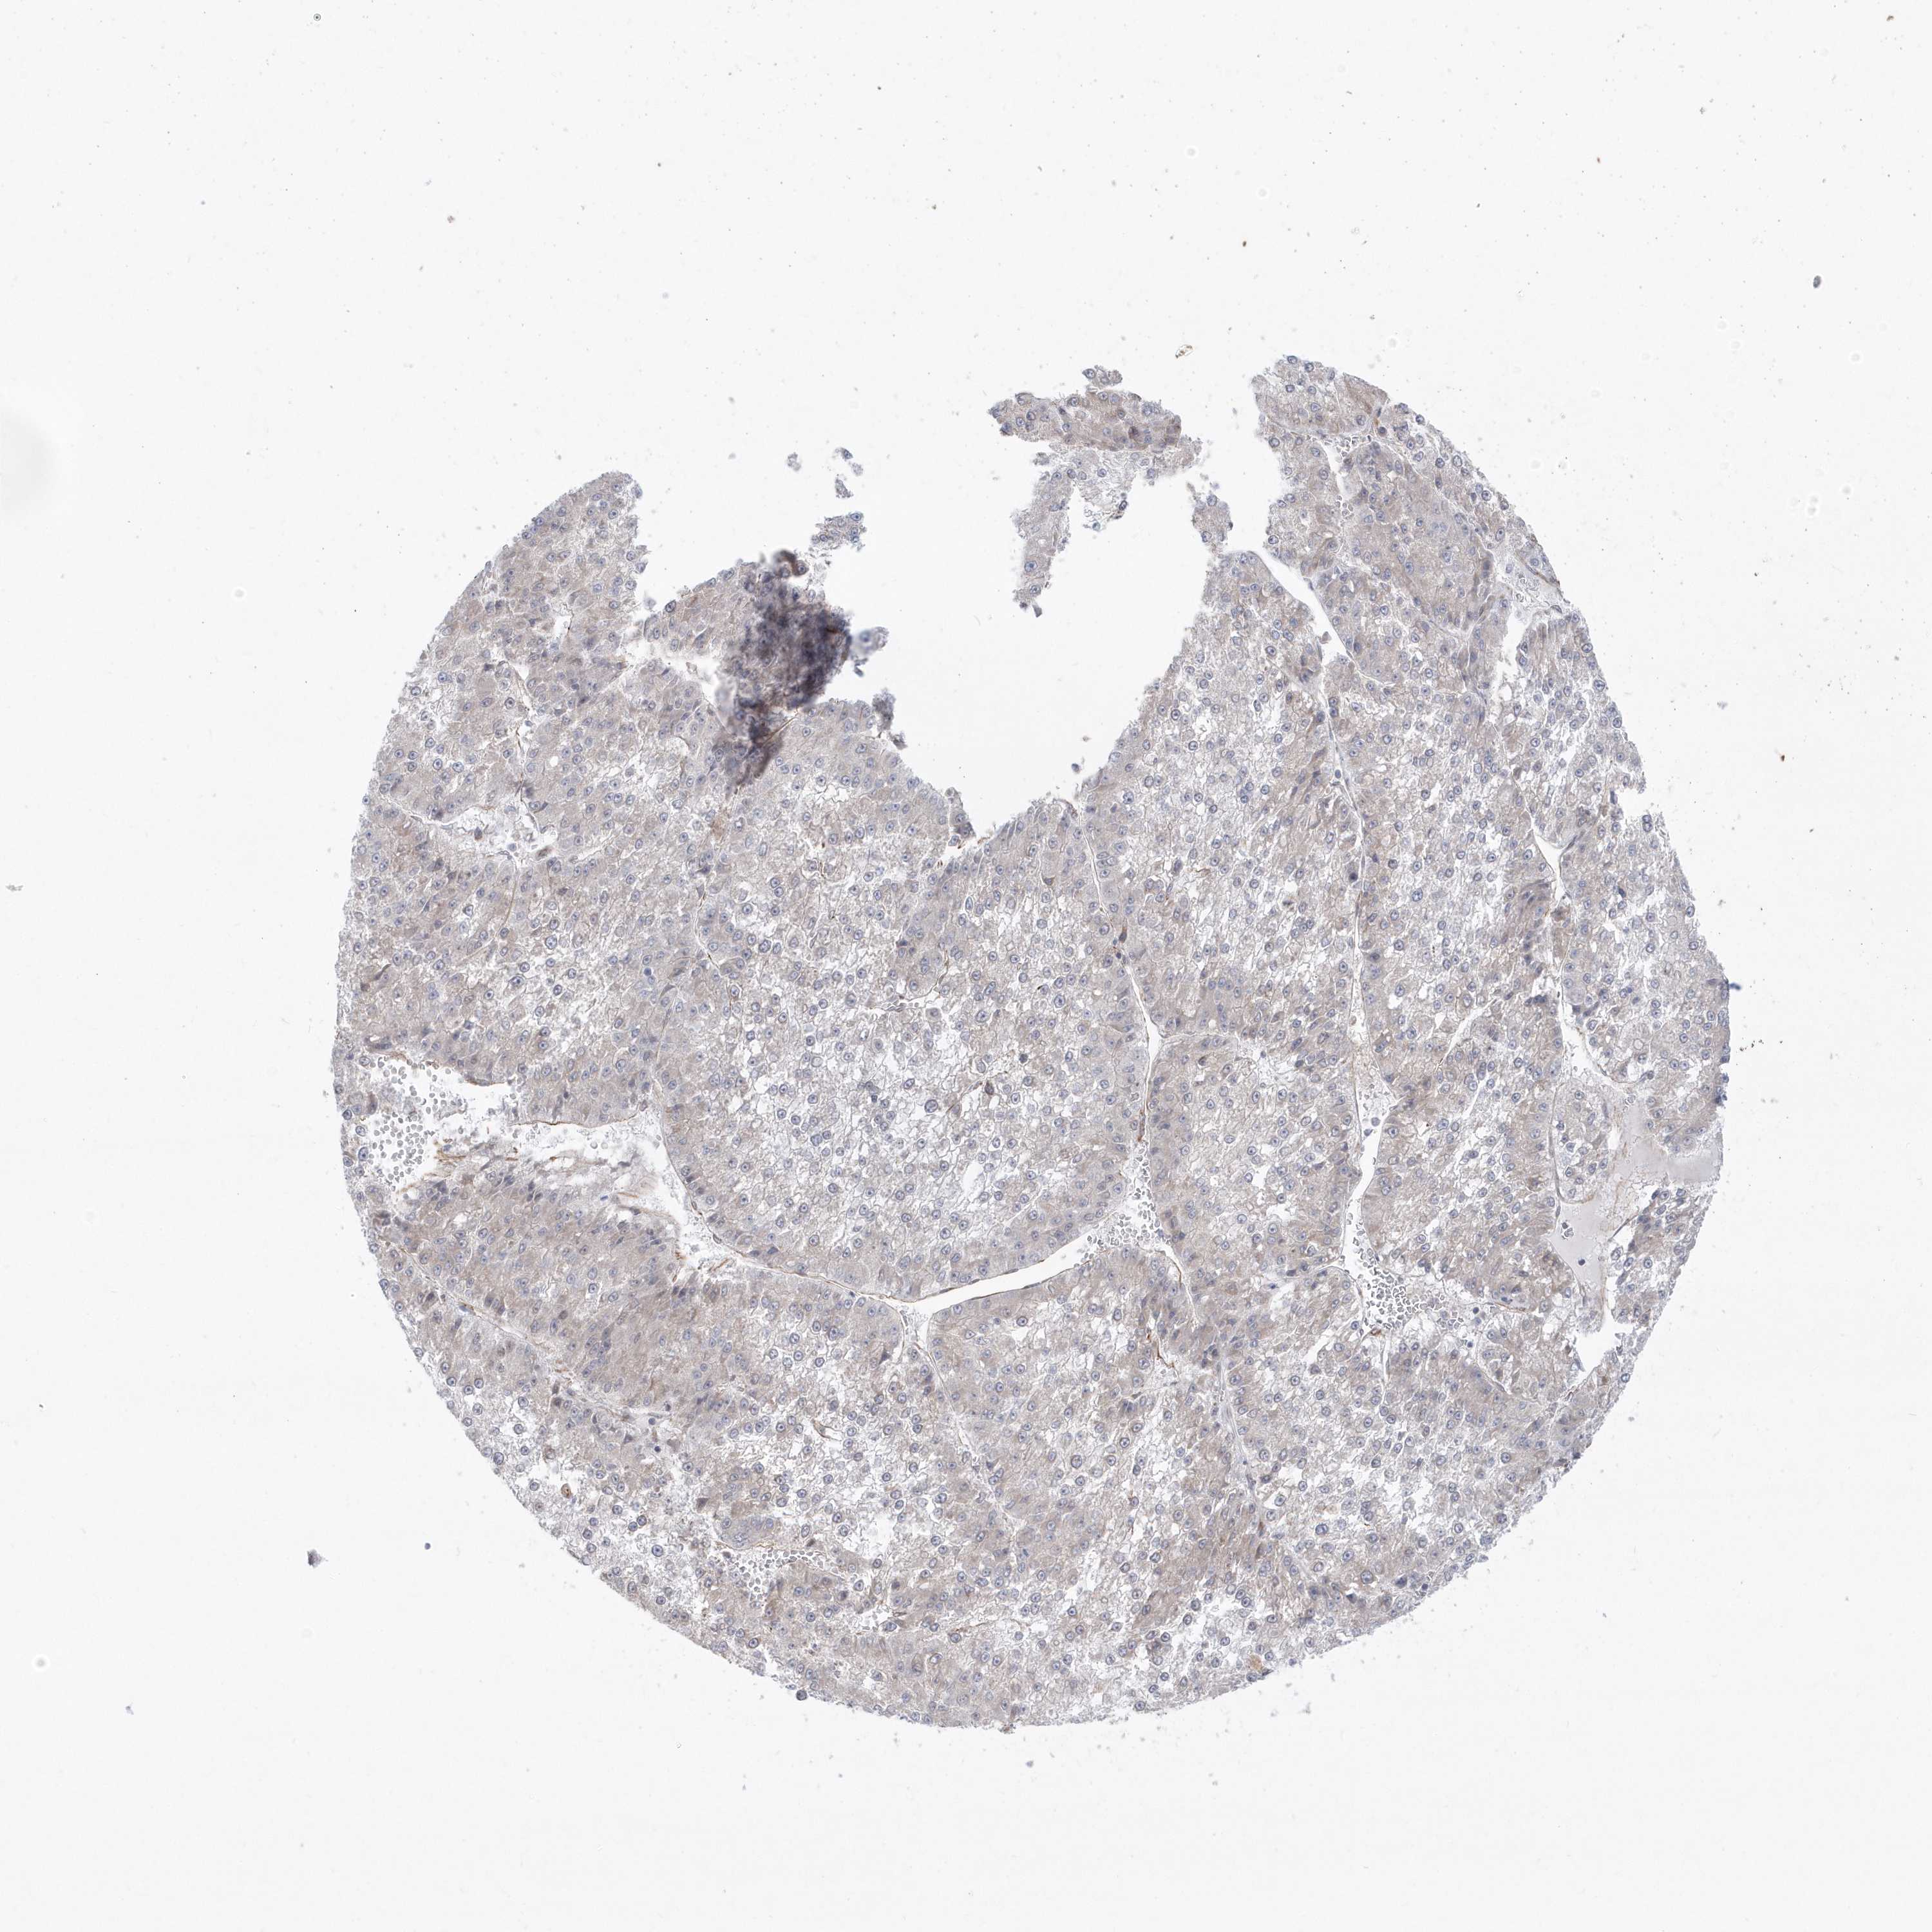

LIVER CANCER - Protein expressioni

A mouse-over function shows sample information and annotation data. Click on an image to view it in a full screen mode. Samples can be filtered based on level of antibody staining by selecting one or several of the following categories: high, medium, low and not detected. The assay and annotation is described here.

Note that samples used for immunohistochemistry by the Human Protein Atlas do not correspond to samples in the TCGA dataset.

Antibody stainingi

Antibody staining in the annotated cell types in the current human tissue is reported as not detected, low, medium, or high, based on conventional immunohistochemistry profiling in selected tissues. This score is based on the combination of the staining intensity and fraction of stained cells.

Each image is clickable and will lead to virtual microscopy that enables deeper exploration of all samples and also displays staining intensity scores, fraction scores and subcellular localization as well as patient and tissue information for each sample.

Antibody HPA036160

Staining

High

Medium

Low

Not detected

Intensity

Strong

Moderate

Weak

Negative

Quantity

>75%

75%-25%

<25%

None

Location

Nuclear

Cytoplasmic/membranous

Cytoplasmic/membranous,nuclear

Cholangiocarcinoma

Carcinoma, Hepatocellular, NOS